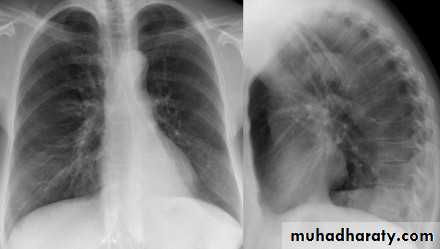

Normal chest XR PA & lateral view

Look carefully on both diaphragmatic cruse costo & cardio phrenic angles

Don't forget to use rib in asses lung Zones

1,2,3 .presentation4.normal chest film ( PA ) view

5.PA vs AP view

6.lateral film position

7.decubitus film

8.normal chest XR PA & lat. view

9.normal radiologic anatomy of the chest

10.normal chest anatomy

11.Radiological lung zone

12.sequence for XR reading